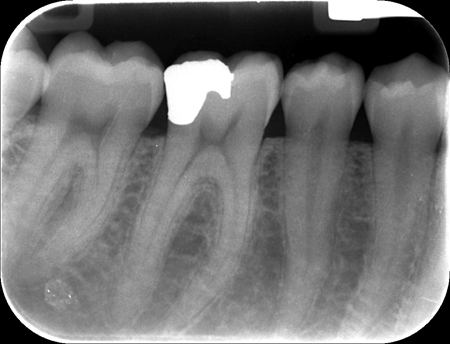

Case 1: Severe Curvature in Upper Bicuspid

قبل / pre

بعد / post